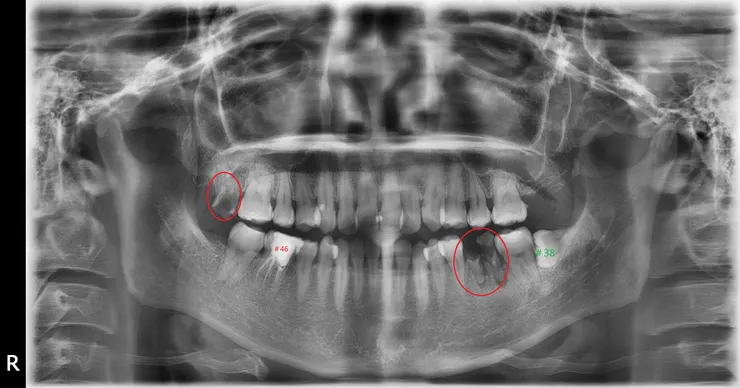

紅圈是非拔不可的牙齒,蛀到剩殘根(R.R.),這部分比較沒有異議。